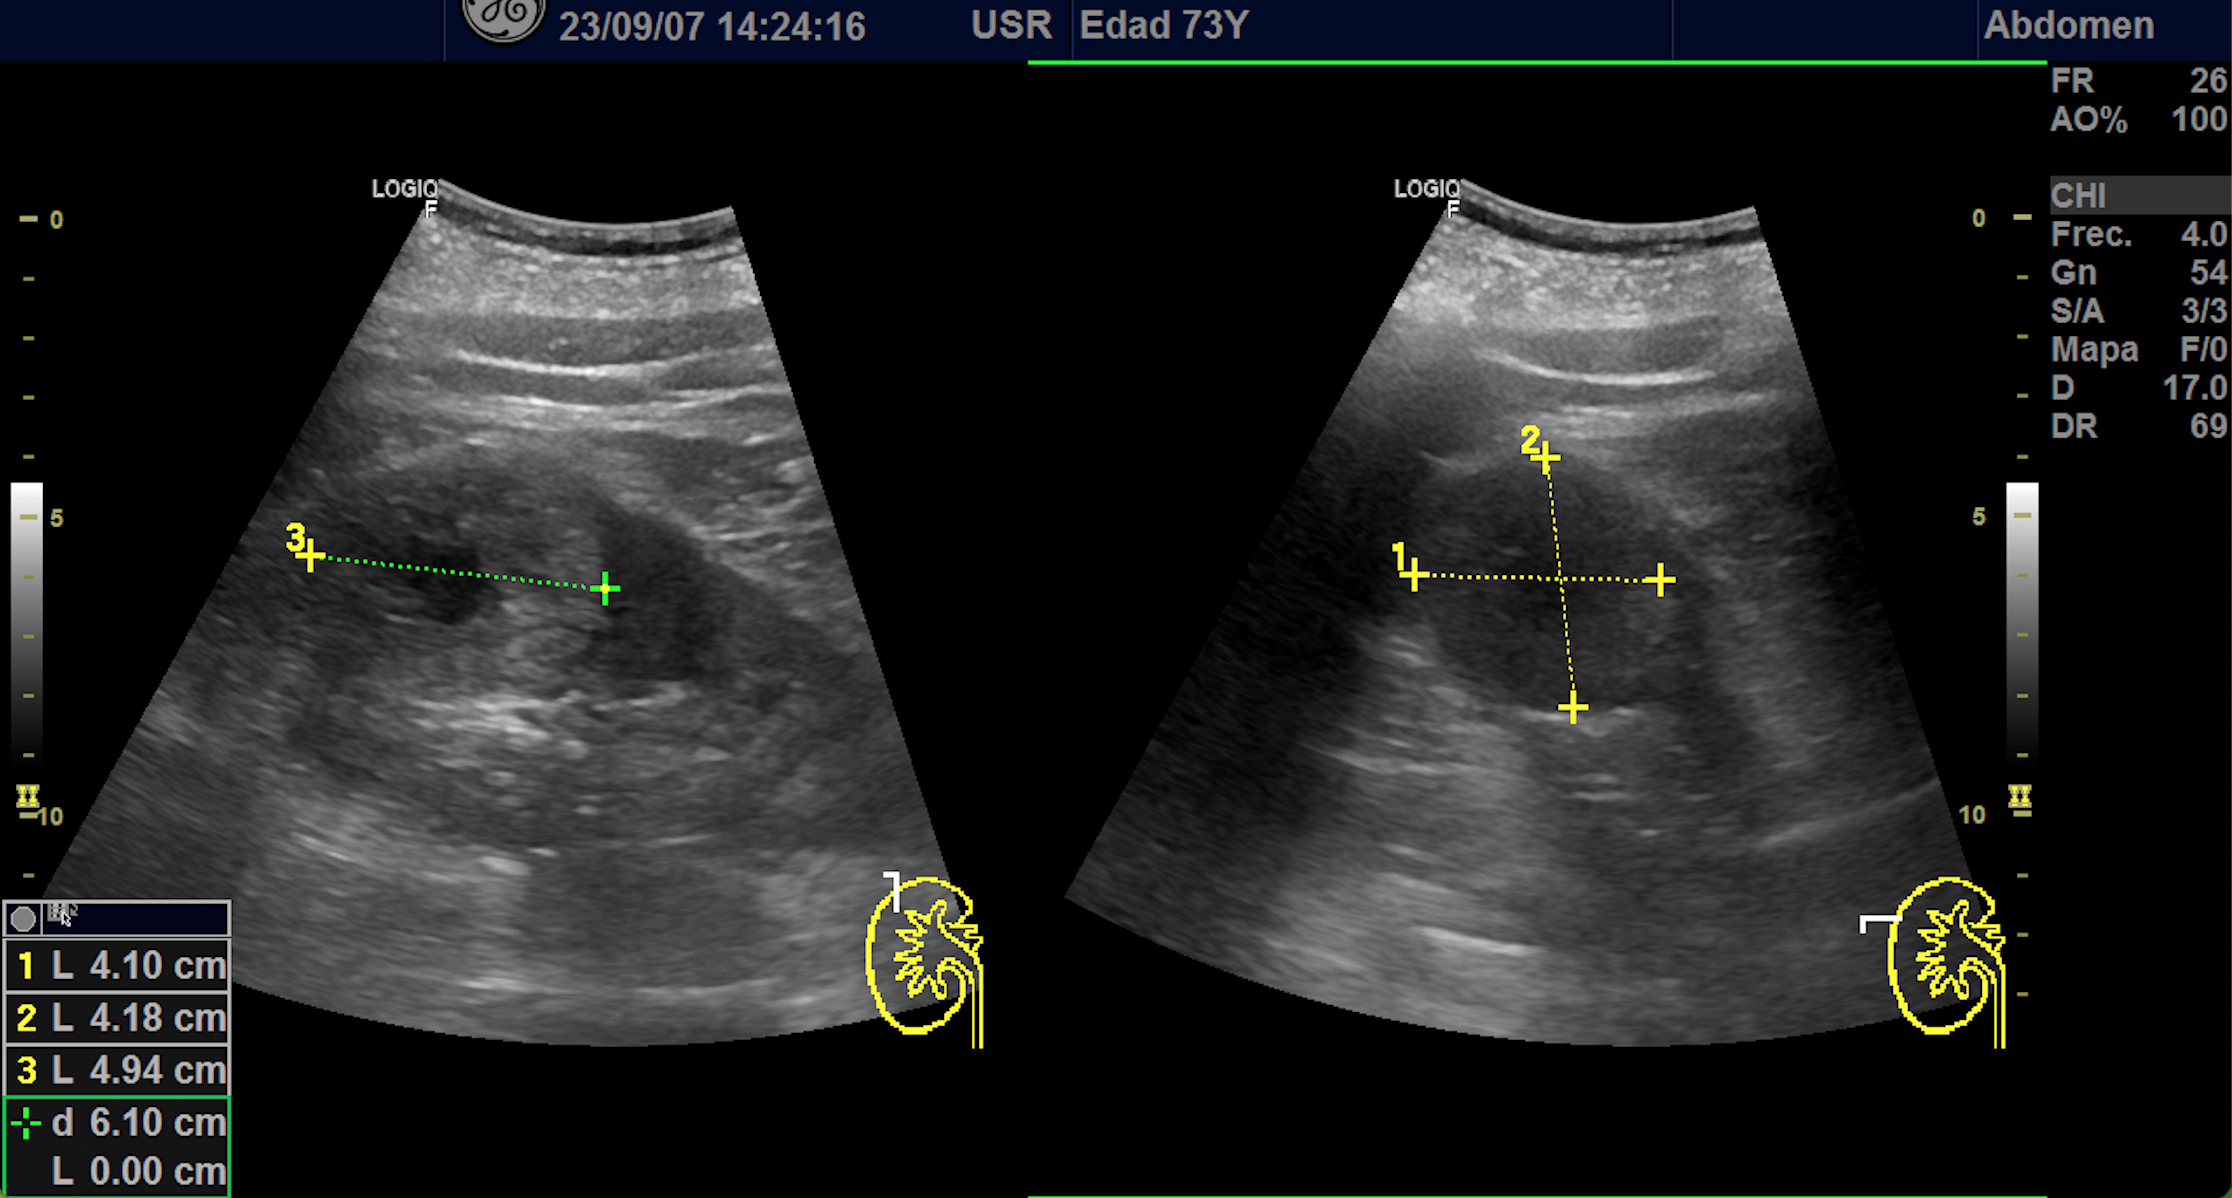

Hallazgos ecográficos

En polo superior de riñón derecho se observa una imagen redondeada, bien delimitada, isoecoica con un área central hipoecoica con vascularización periférica y central de 4,1 x 4,18 x 4,94 cm.

Riñon izquierdo sin hallazgos.